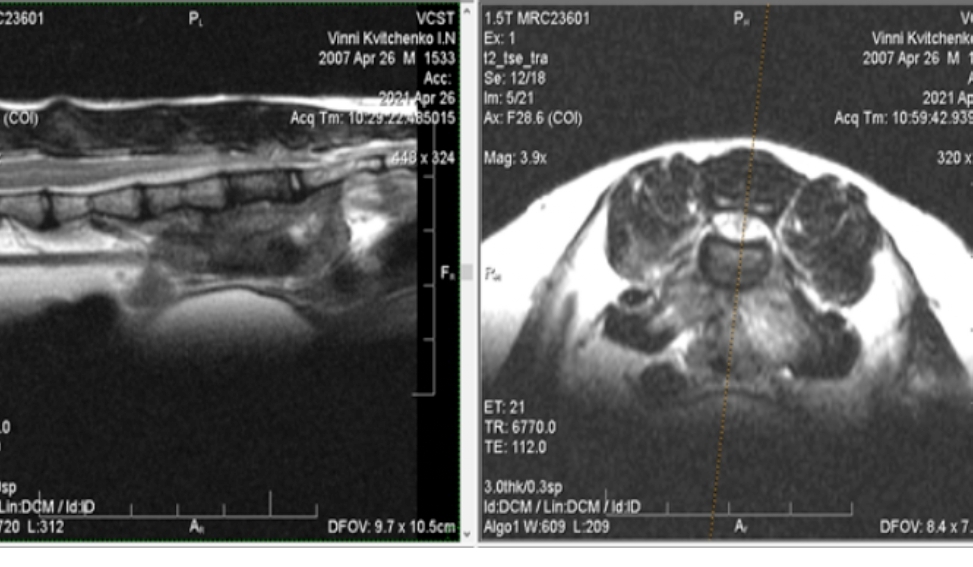

Прежде всего, необходимо произвести специальную диагностику. Рентгеновское исследование неспособно дать все необходимые сведения, как правило, требуется проанализировать результаты компьютерной и магнитно-резонансной томографии, обычно использующиеся в ветеринарной неврологии и отличающиеся более высокой точностью.